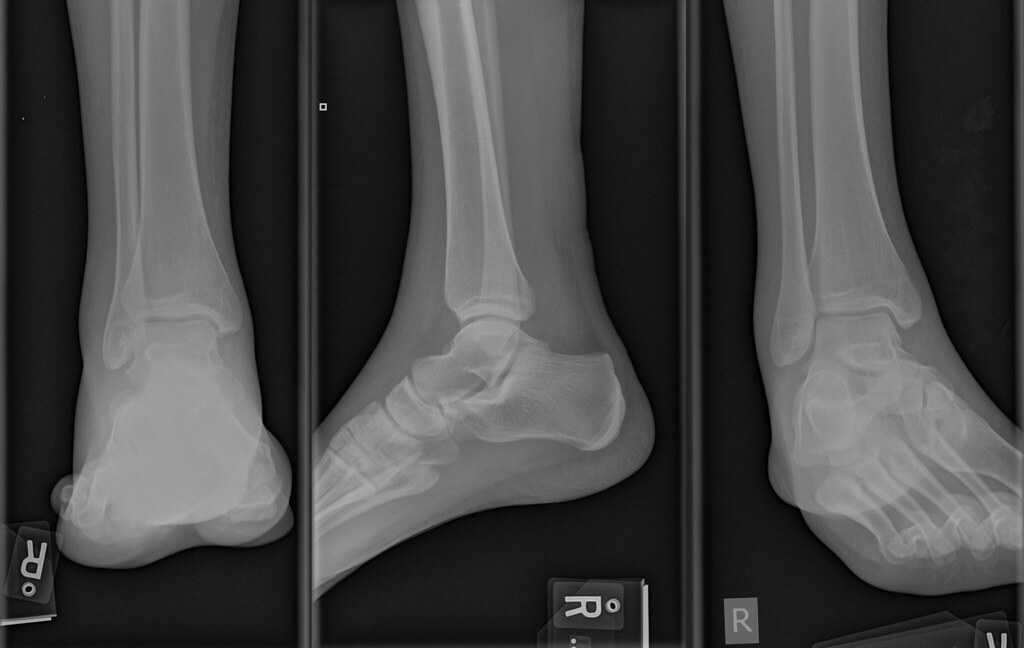

Figure 1 From Stress Fracture Of The Ulna In A Softball